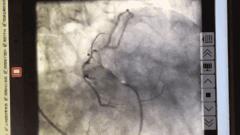

血管开通后造影